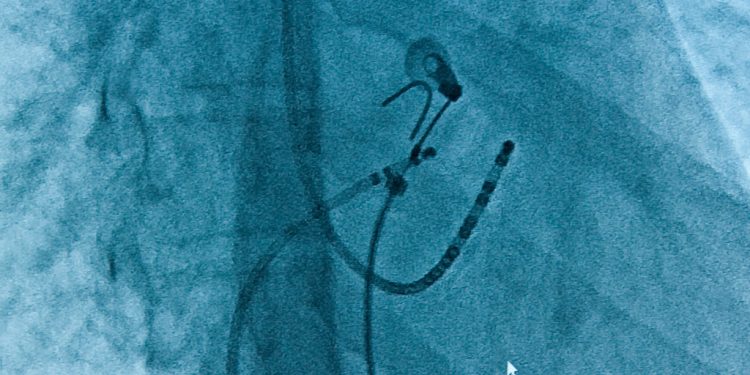

L’ablazione è per sempre con il catetere rivestito in diamante. Stiamo parlando di DiamondTemp di Medtronic, un catetere per l’ablazione del tessuto cardiaco che permette un controllo in tempo reale della temperatura ed altissima qualità del segnale elettrico. Maggiore precisione e tempi di intervento ridotti sono le caratteristiche innovative di questo dispositivo, l’unico a radiofrequenza (RF) con controllo della temperatura ogni 20 ms, in grado di interrompere permanentemente le aritmie cardiache in modo sicuro ed efficace grazie alla rapida conduzione di energia termica, resa possibile dal rivestimento in diamante industriale.

L’evoluzione tecnologica introdotta dal sistema DiamondTemp, aumenta la precisione del trattamento ablativo e permette di trattare tutti i pazienti grazie alla disponibilità di 4 differenti modelli di catetere. Un ulteriore passo avanti nel trattamento delle aritmie cardiache grazie all’utilizzo di una tecnologia e di materiali all’avanguardia che consente di eliminare in modo permanente le aritmie siano esse tachicardie ventricolari o tachiaritmie sopraventricolari, tra cui anche la fibrillazione atriale.

Rispetto ai metodi convenzionali, la procedura con il nuovo sistema DiamondTemp è particolarmente efficiente poiché fornisce in modo tanto veloce quanto preciso il dato della temperatura rilevata grazie ai sei minuscoli sensori posti sulla punta del catetere che garantiscono una lettura della temperatura reale raggiunta. Se necessario il sistema modula automaticamente la potenza, mentre il rivestimento con diamante industriale consente un raffreddamento uniforme e il mantenimento della temperatura terapeutica ottimale. La nuova tecnologia DiamondTemp, appositamente costruita per l’ablazione con il vero controllo di temperatura, migliorerà la qualità dei trattamenti e ridurrà la necessità di ablazioni ripetute, comportando quindi un grande passo avanti nel campo dell’elettrofisiologia del terzo millennio.